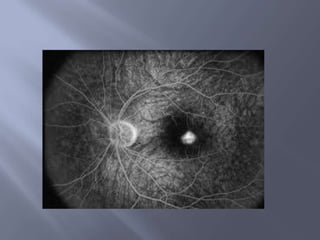

2. Affirmer de l’ OP :Elargissement : taille  sup à deux cm Bord flou Saillie de bord papillaire / rétine         aspect en arc des vaisseaux  rétiniens Comblement de l’excavation physiologique Distension et trajet tortueux des veines centrales de la rétine Hémorragie  minime en péri papillaire  Exsudats parfois

3.AFFIRMER LE CARACTERE  PUR  DE L’OP  :  bilatéral

Champs visuel élargissement de la tache de Mariotte avec absence de déficit systématisé Stades   I : OP au debut      floue terne limites imprecises hyperhémie papillaire veines congestionnés

Oedèmes papillaires purs